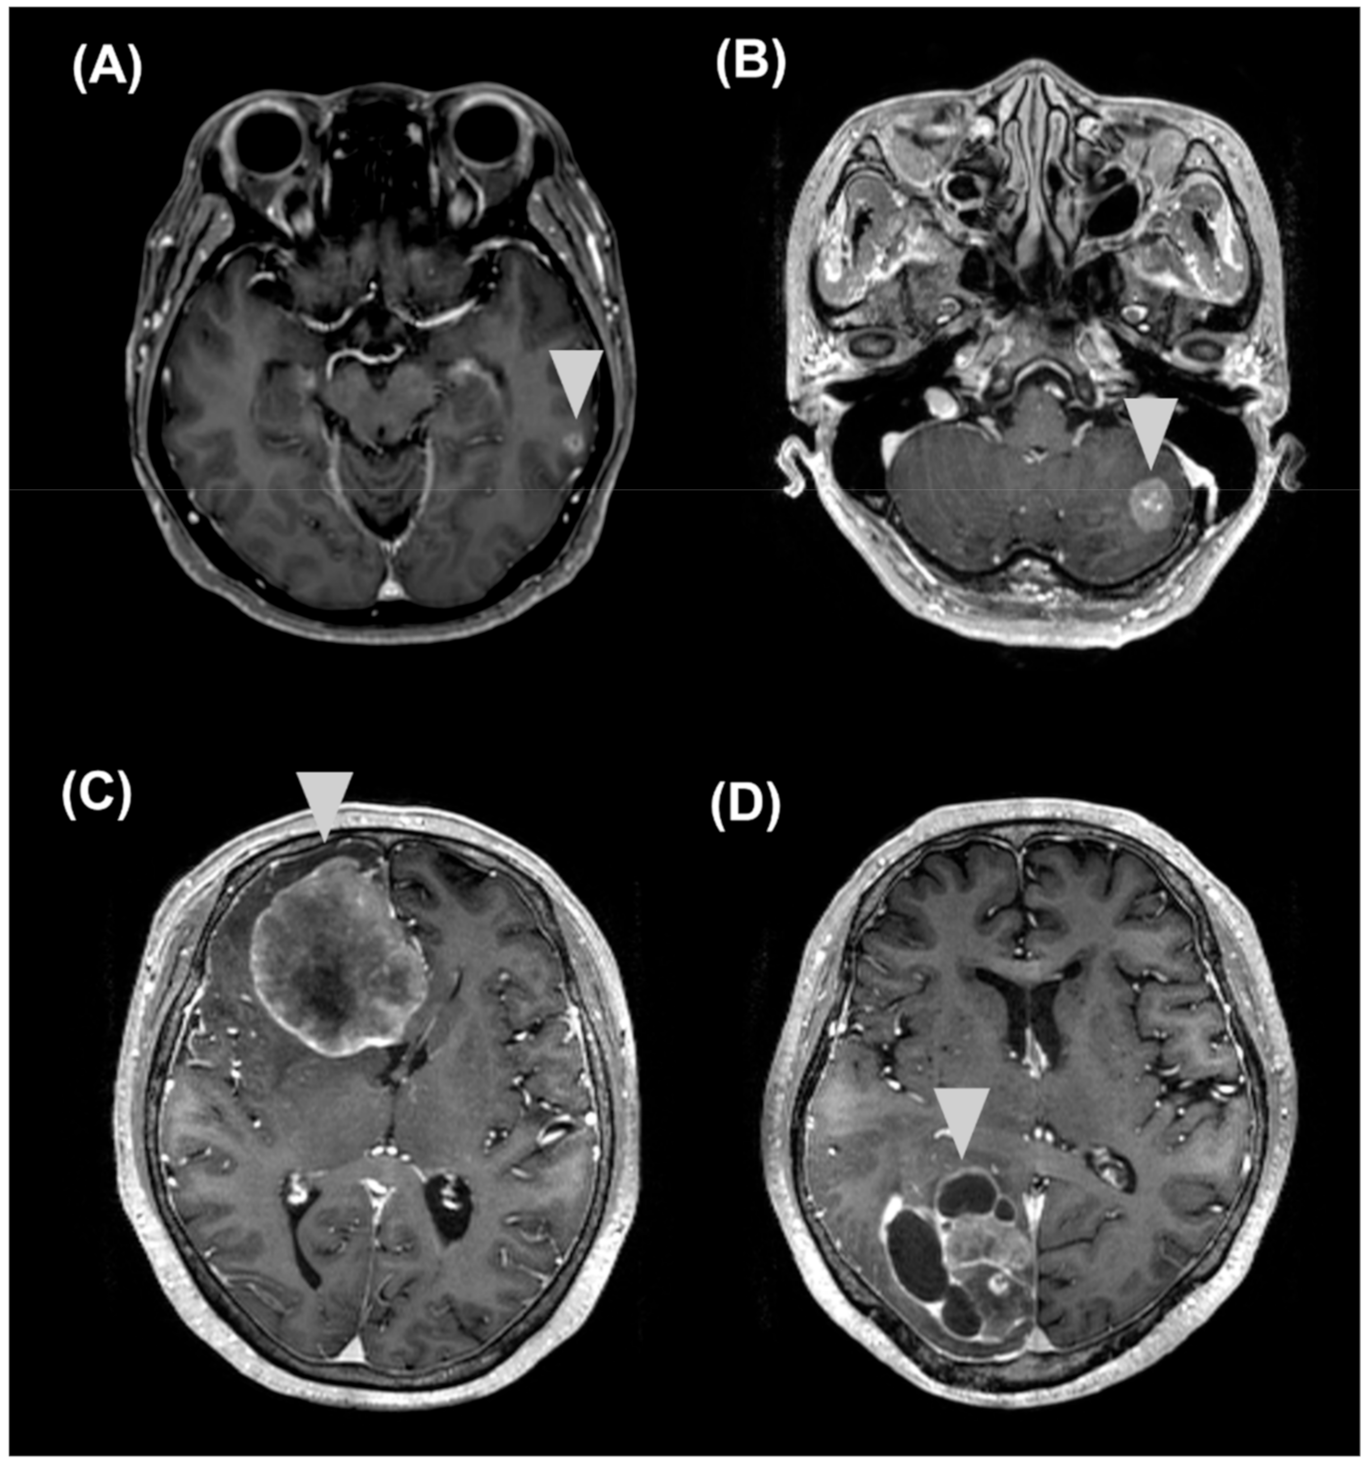

2.5. Longitudinal Follow-Up